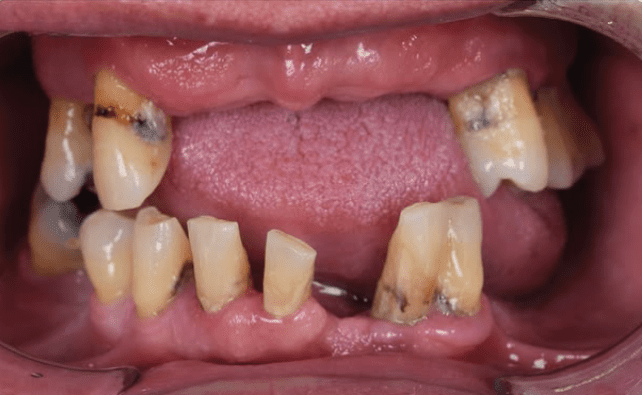

Tooth loss can feel overwhelming but waiting months for a replacement doesn’t have to be part of the process. With immediate dental implants, you can often replace a missing tooth on the very same day it’s removed, restoring your smile, comfort, and confidence without delay.

At Summirow Dental Hospital, we offer advanced immediate implant solutions designed for patients who qualify for fast, reliable tooth replacement with natural-looking results. Immediate dental implants are placed directly into the jawbone at the time of tooth extraction.

Instead of waiting weeks or months for healing before implant placement, both steps are completed in a single visit. This technique helps preserve jawbone structure, maintain healthy gum contours, and significantly shorten the overall treatment time- making Summirow a preferred choice for the Best Immediate Dental Implants in Surat.